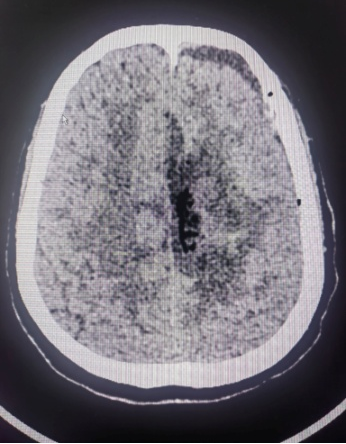

患者系中年女性,因出现偏侧肢体活动不灵和头痛症状,经检查发现颅内大脑镰旁长有一直径7cm的巨大肿瘤。肿瘤位于大脑的运动功能区,血供丰富,这一区域的手术风险极大。在决定手术治疗之前,神经外科医生与患者家属进行了充分的沟通,详细解释了手术的必要性、可能的风险和并发症,包括出血、感染、血管和神经损伤以及脑功能障碍等。家属在充分了解情况后,同意进行手术。面对这一复杂病例,我院迅速组织了由神经外科、麻醉科、心内科、输血科等多个科室的专家团队进行会诊,共同制定了先介入栓塞,再手术切除的治疗方案。

神经外科血管介入组曲友直副教授、崔刚副教授和高攀主治医师对肿瘤进行了瘤栓塞治疗,有效减少了肿瘤的血供,为后续的手术切除降低了风险。栓塞治疗后,神经外科王睿智副主任、高李贵副教授和董全主治医师在麻醉科、心内科、输血科等科室的全力配合下,凭借精湛的医术和丰富的临床经验,成功为患者切除了病变。手术过程中,麻醉科吕建瑞主任团队全程监控患者的生命体征,确保麻醉安全;心内科团队随时准备应对可能出现的心脏问题;输血科团队则确保充足的血液供应,以备不时之需。多学科的通力合作,为手术的成功提供了坚实的保障。

术后,患者被送至NICU进行密切观察,神经外科护理团队提供了精心的护理服务。在医护人员的共同努力下,患者恢复平稳,未出现任何并发症,并于近日顺利出院。